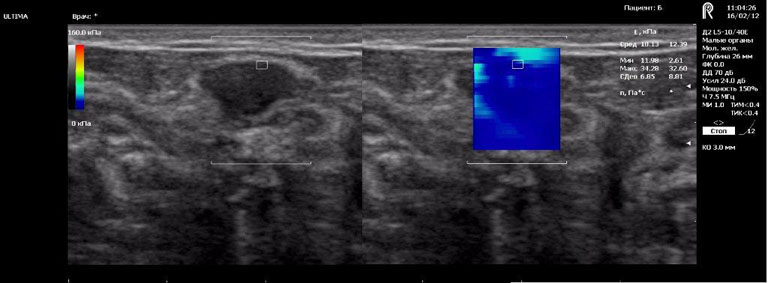

Після комп’ютерної обробки інформація передається на екран монітора, де ділянки з різними механічними властивостями відображаються різним кольором. Таке зображення називається «еластограма». В досліджуваному об’ємі тканин можливо провести кількісні вимірювання і, шляхом порівняння з еталонними значеннями, зробити висновок про наявність патології і її характер. Більш жорсткі тканини відображаються червоним, а м’які — синім кольором. Висока жорсткість утвору при проведенні еластографії свідчить про високу вірогідність його злоякісного походження.

Ехограми

Breast fibroadenoma (доброякісна пухлина)